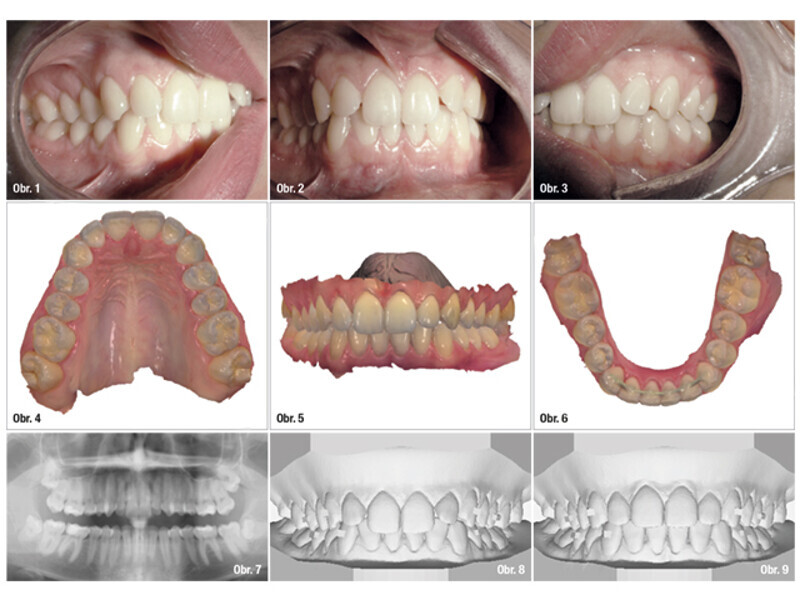

Malokluze I. třídy léčená pomocí F22 Aligners